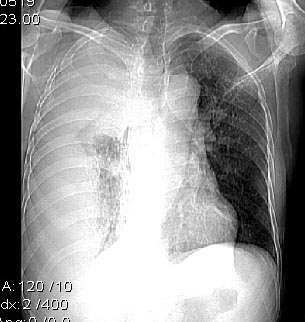

男,76岁,因心累,气紧加重,伴吐白色沫哝痰,偶尔有低烧,无盗汗。{门诊患者未见其它检查}

右肺毁损萎陷,其内可见钙化灶、残存空腔及支气管影。左上叶可见多发小结节影。纵隔左移,其内未见肿大淋巴结。右侧胸腔大量积液。考虑:肺结核并右肺毁损;右侧胸腔大量积液。

右侧大量胸腔积液伴右肺压迫性肺不张,上叶内是不是结核灶?

包裹性积液,并右侧肺不张

一看这个病人的定位片大致倾向恶性病变,因胸水漫顶,纵隔少偏.右上肺门旁肿块肯定,肺内肿瘤可能性很大.右上肺病灶多为陈旧性结核.实际上结核病并发肿瘤并非少见.所以二元论诊断也不奇怪.